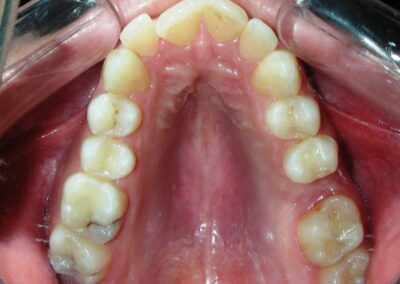

Was installed a Hyrax-type 10mm palatal expander of the Brazilian trademark Morelli® , modified by the author to be adapted to receive TADs microscrews, in order to initiate maxillary disjunction with MARPE (Mini-implant Assisted Rapid Palatal Expansion), TADS was installed with skeletal anchorage placed bilaterally having as references the roots of the maxillary canines and first premolars. Prior to insertion, local infiltrative anesthesia was administered using 2% lidocaine hydrochloride with 1:100,000 epinephrine. A total dose of approximately 0,8 mL per side (cortical infiltration technique). The TADs were inserted under aseptic conditions using a manual driver. Microscrew Evolution 1,6 Ø x 10 mm from the Argentine brand Odontit® . The Hyrax expander was then fitted and activated after 48 hrs .

Protocol of one activation per day was followed for a period of three weeks where the first clinical and radiographic evaluation was performed, showing clear signs of skeletal expansion, including the presence of a midline diastema. One more week of activations was added with a total of 28. The patient reported moderate headache during the first week of activation.